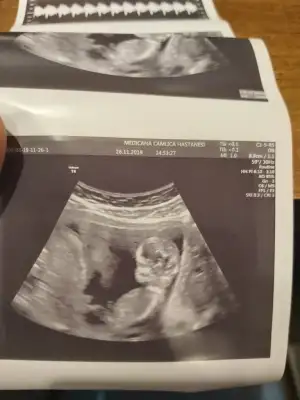

12+1 bugünE

Buna da bakarmısınız 11+5 arkadaşın

13. Haftalık 11 ve 12. Haftalıkken doktora gitmedik kontrolümüz 13. Haftaya denk geldi o yüzden bu başka da var ama net değil ki atayım ben yine deerkek gibi başka usg var kaç haftalık